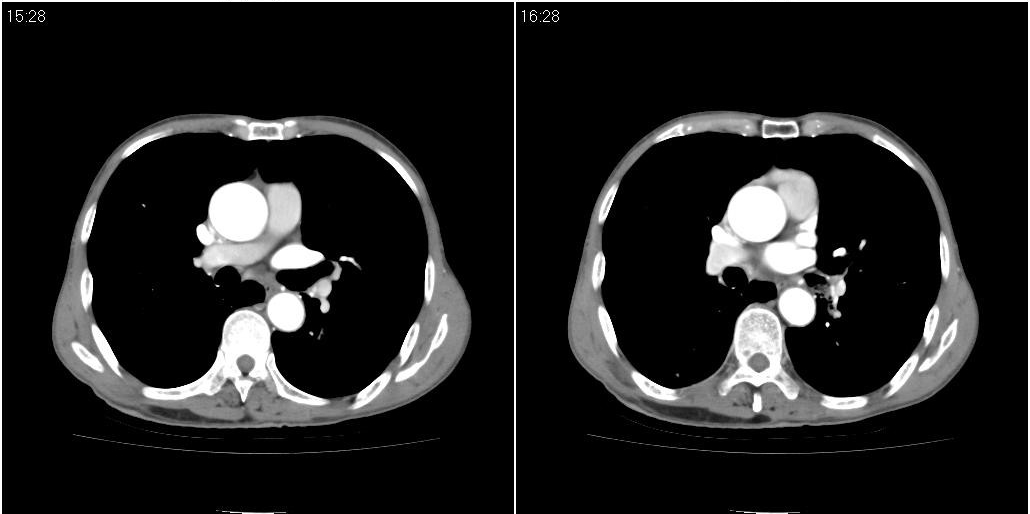

标题: CT25416:男性,70岁。胸片发现右下肺斑片状阴影

以下是ct检查的情况:

标题: ct增强:

右肺中叶阻塞性不张及肺炎,高度怀疑支气管占位,建议纤支镜检查!

右中肺阻塞性炎症,建议纤支镜!双下支扩感染。